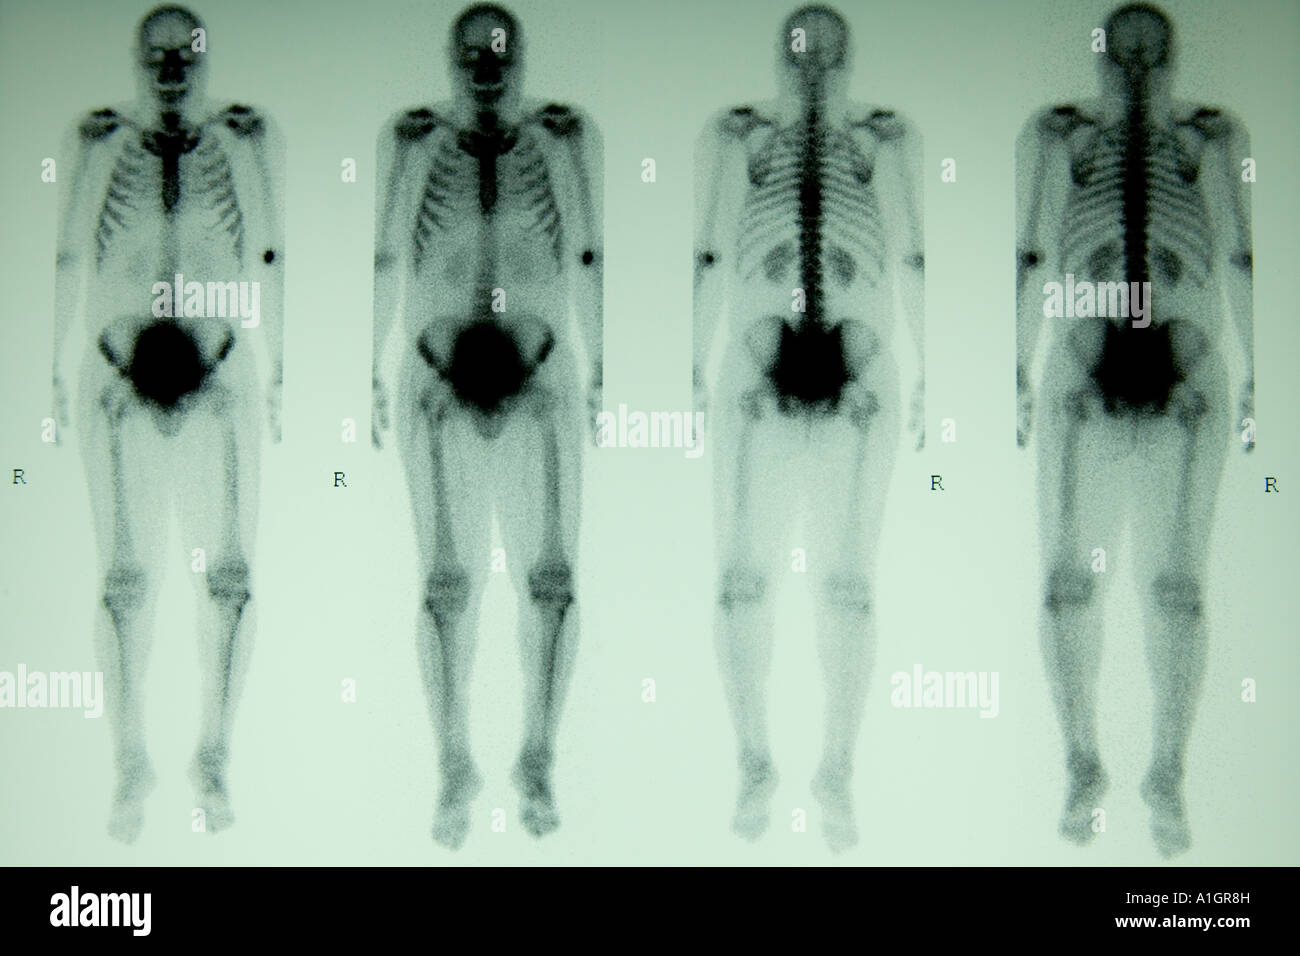

La scintigraphie osseuse, corps complet, de la phase trois Banque D'Imageshttps://www.alamyimages.fr/image-license-details/?v=1https://www.alamyimages.fr/photo-image-la-scintigraphie-osseuse-corps-complet-de-la-phase-trois-10256272.html

La scintigraphie osseuse, corps complet, de la phase trois Banque D'Imageshttps://www.alamyimages.fr/image-license-details/?v=1https://www.alamyimages.fr/photo-image-la-scintigraphie-osseuse-corps-complet-de-la-phase-trois-10256272.htmlRMA1GR8H–La scintigraphie osseuse, corps complet, de la phase trois